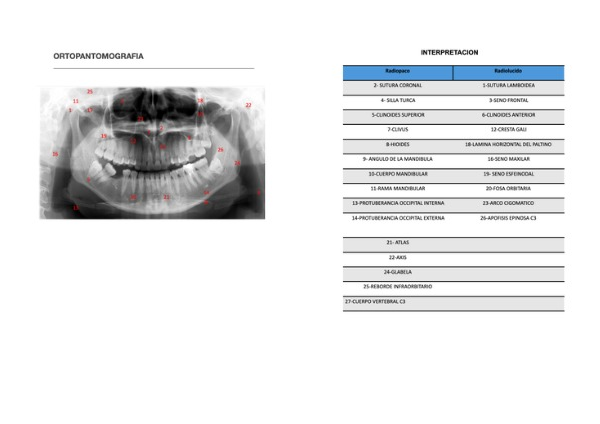

revista radiologica RADIOLOGIA- CALIXTO ALFARO JOSE LUIS | Page 24

revista radiologica RADIOLOGIA- CALIXTO ALFARO JOSE LUIS | Page 23

revista radiologica RADIOLOGIA- CALIXTO ALFARO JOSE LUIS | Page 25